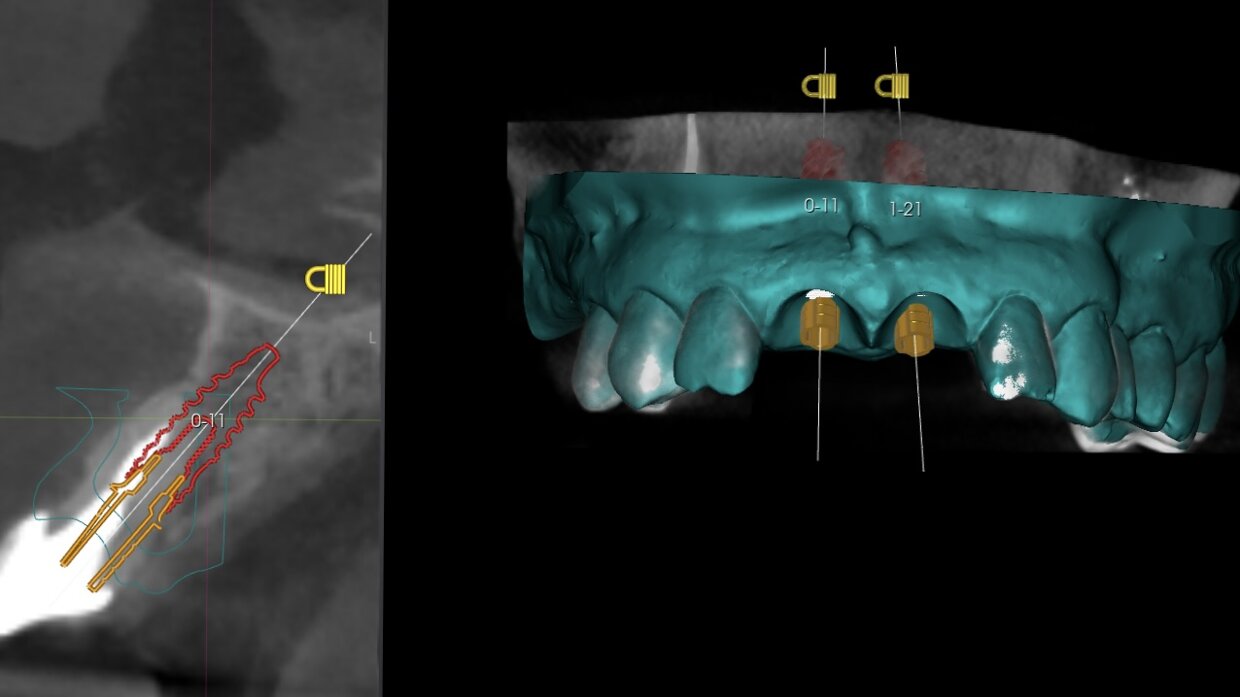

Il posizionamento degli impianti è stato pianificato prima dell'intervento su un software dedicato. In un'unica seduta, dopo l'estrazione degli elementi dentari compromessi, sono stati immediatamente inseriti gli impianti nella posizione pianificata, grazie alla realizzazione della dima chirurgica. Per ridurre il riassorbimento osseo a lungo termine e garantire quindi una maggiore resa estetica (vista la zona d'intervento), la chirurgia è stata eseguita con una particolare tecnica denominata: Socket Shield Technique.

Scopri quali sono i passaggi per la pianificazione digitale degli impianti